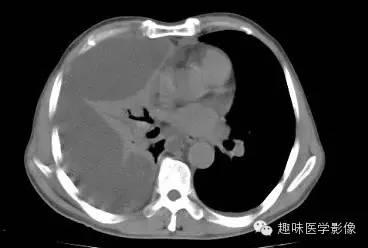

CT: 右侧胸廓缩小。右肺上叶前段结节,略分叶,可见长短不一毛刺,胸膜牵拉征及血管集束征,右肺组织向肺门萎陷,左肺清晰,未见异常。纵隔内见淋巴结肿大(4R淋巴结增大)。右侧前壁及侧后胸壁包裹性积液征象。

右上肺周围型肺癌,纵隔淋巴结转移,胸膜腔包裹性积液。